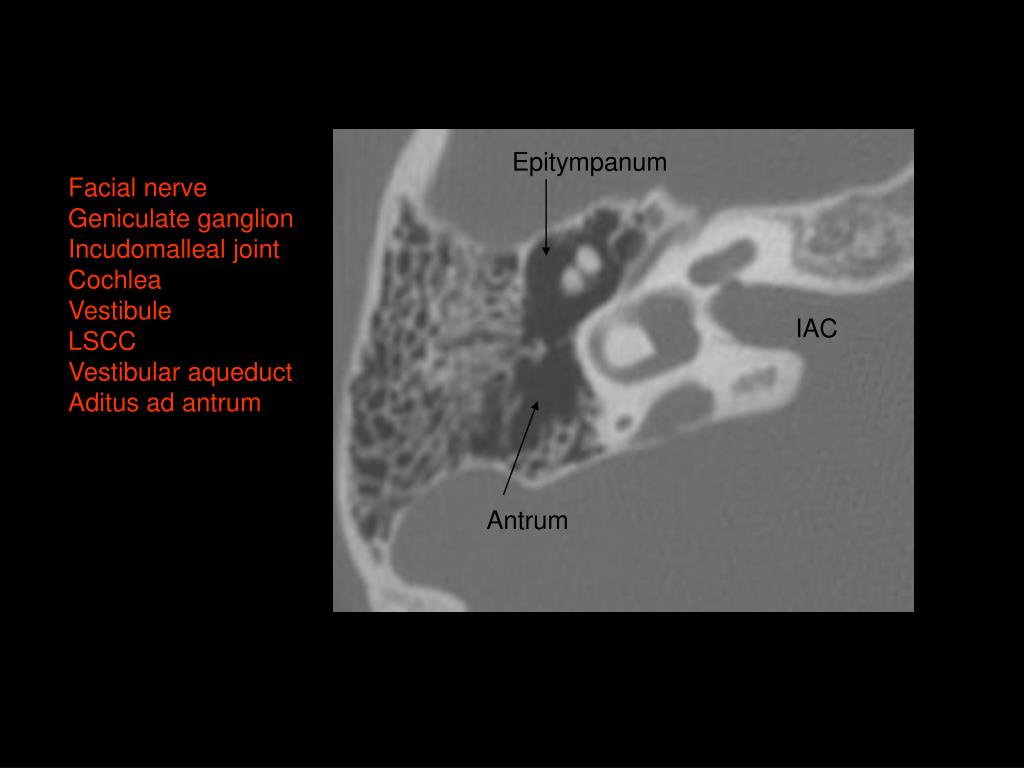

13. Antrum Vestibule SSCC LSCC Facial nerve

28. Geniculate ganglion Cochlea Vestibule Vestibular aqueduct IAC Antrum